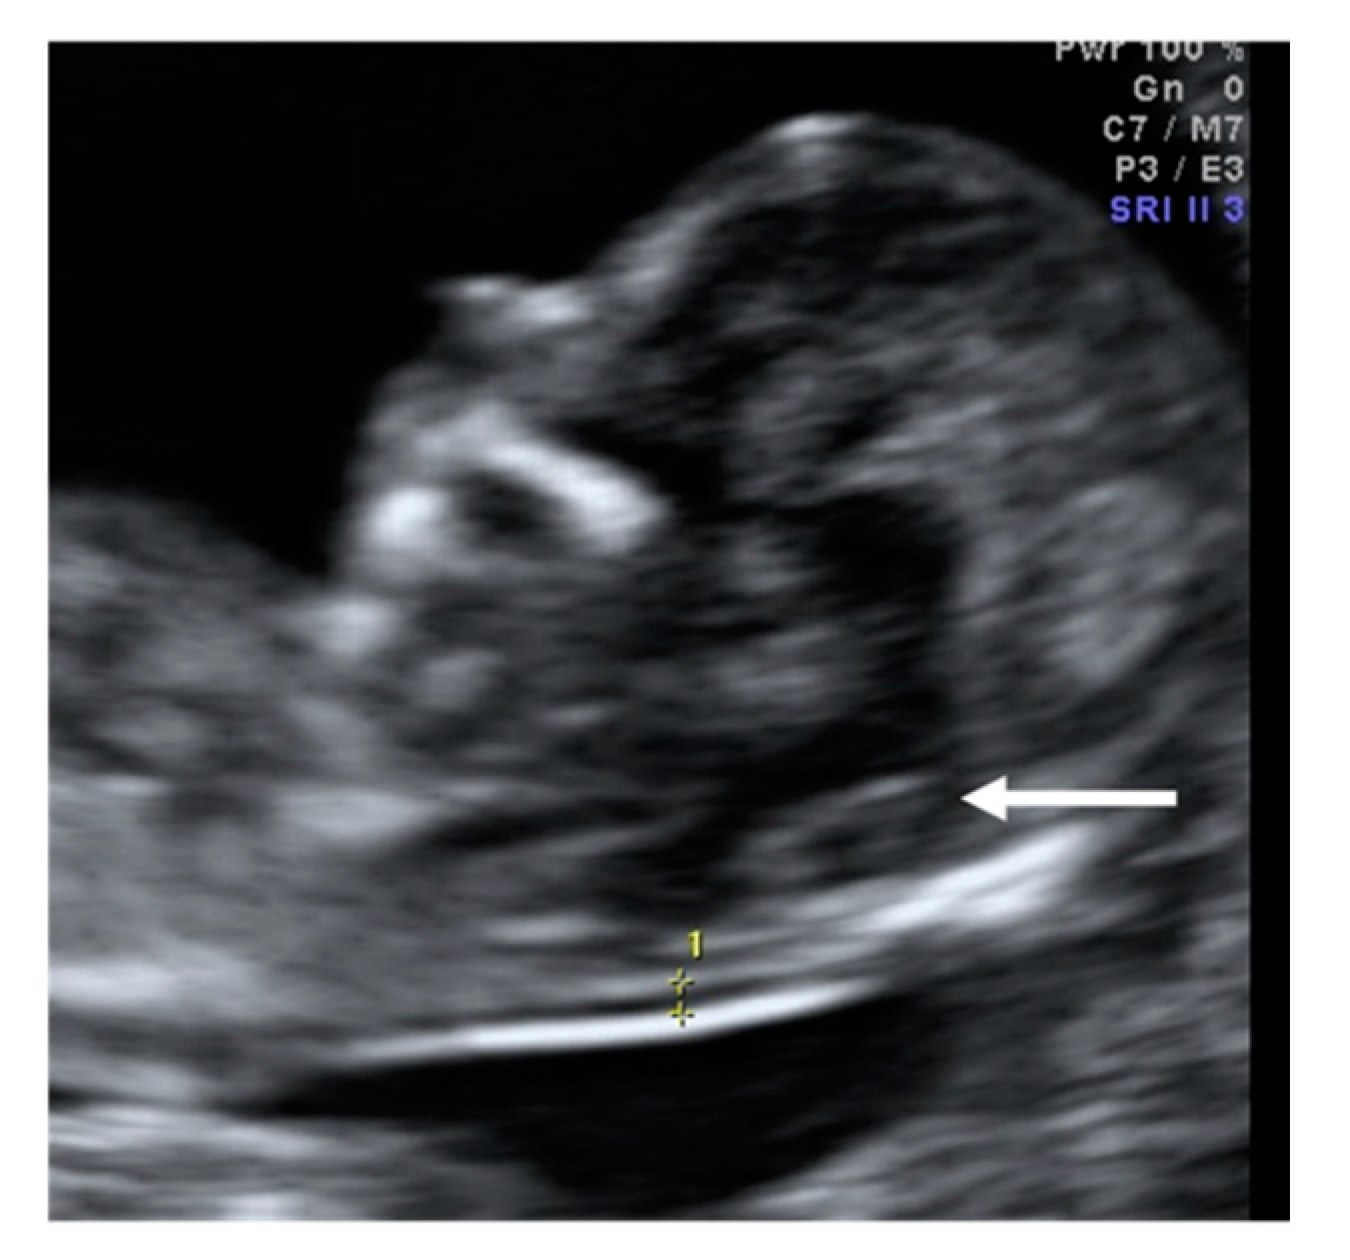

A 30-year-old woman G2 P1 with a history of insulin resistance was referred for first-trimester screening at 12 weeks gestation due to an increased NT. The fetus had a CRL of 56 mm, NT was 2.5 mm, the nasal bone was present, and the absence of the IT was documented. Additional findings included tricuspid regurgitation and suggestive images for congenital heart disease, single umbilical artery, and encephalocele (Figure 7). Due to these findings, the patient was classified as having a high risk for chromosomal anomalies. Invasive diagnostic tests were offered to confirm the suspicion, but the patient opted for termination of pregnancy.

Figure 7. Case 6. The absence of intracranial translucency (IT) and the increase of the brain stem are observed. Additionally, an occipital encephalocele (white arrow) can be observed.